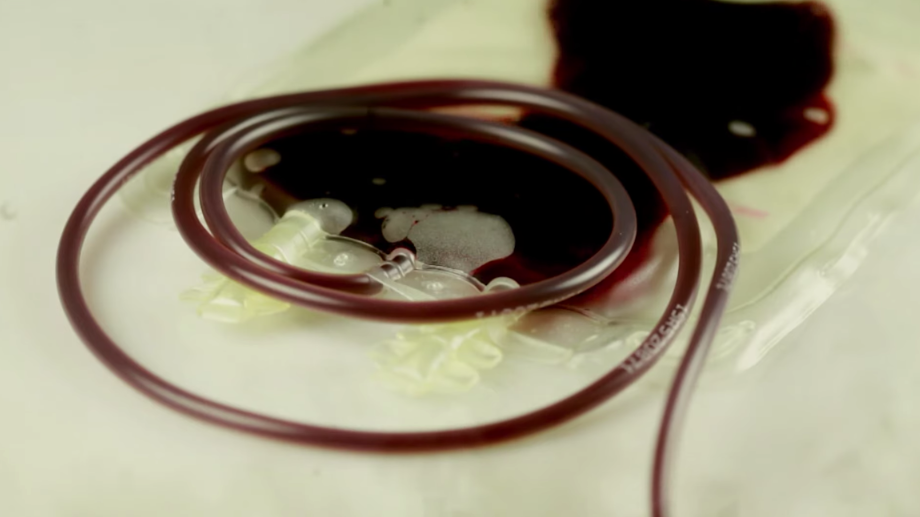

Donar sangre es considerado un acto de generosidad y solidaridad con la sociedad, pues algunos necesitan del preciado líquido para seguir viviendo. Sin embargo, hay empresas que prefieren comprarla, pues un litro de sangre vale 40 veces más que un litro de gasolina.

Aunque parezca inverosímil, no es el rojo de la sangre ni la espesura de su textura lo que determina el costo del líquido vital, lo que en realidad vale es el plasma, un elemento de la sangre rico en proteínas que se ha convertido en el centro del negocio de estas empresas.

Una vez las empresas recolectan la sangre, la fraccionan para extraer un líquido amarillento conocido como plasma sanguíneo y es utilizado para crear nuevos medicamentos, es vendido a grandes compañías farmacéuticas, quienes demandan anualmente más de 80 mil litros al año, según investigaciones del documental.

Este proceso científico de fraccionamiento se llama aféresis, consiste en que la sangre de un donante se puede dividir en componentes únicos para aprovechar de forma selectiva las plaquetas o plasma.